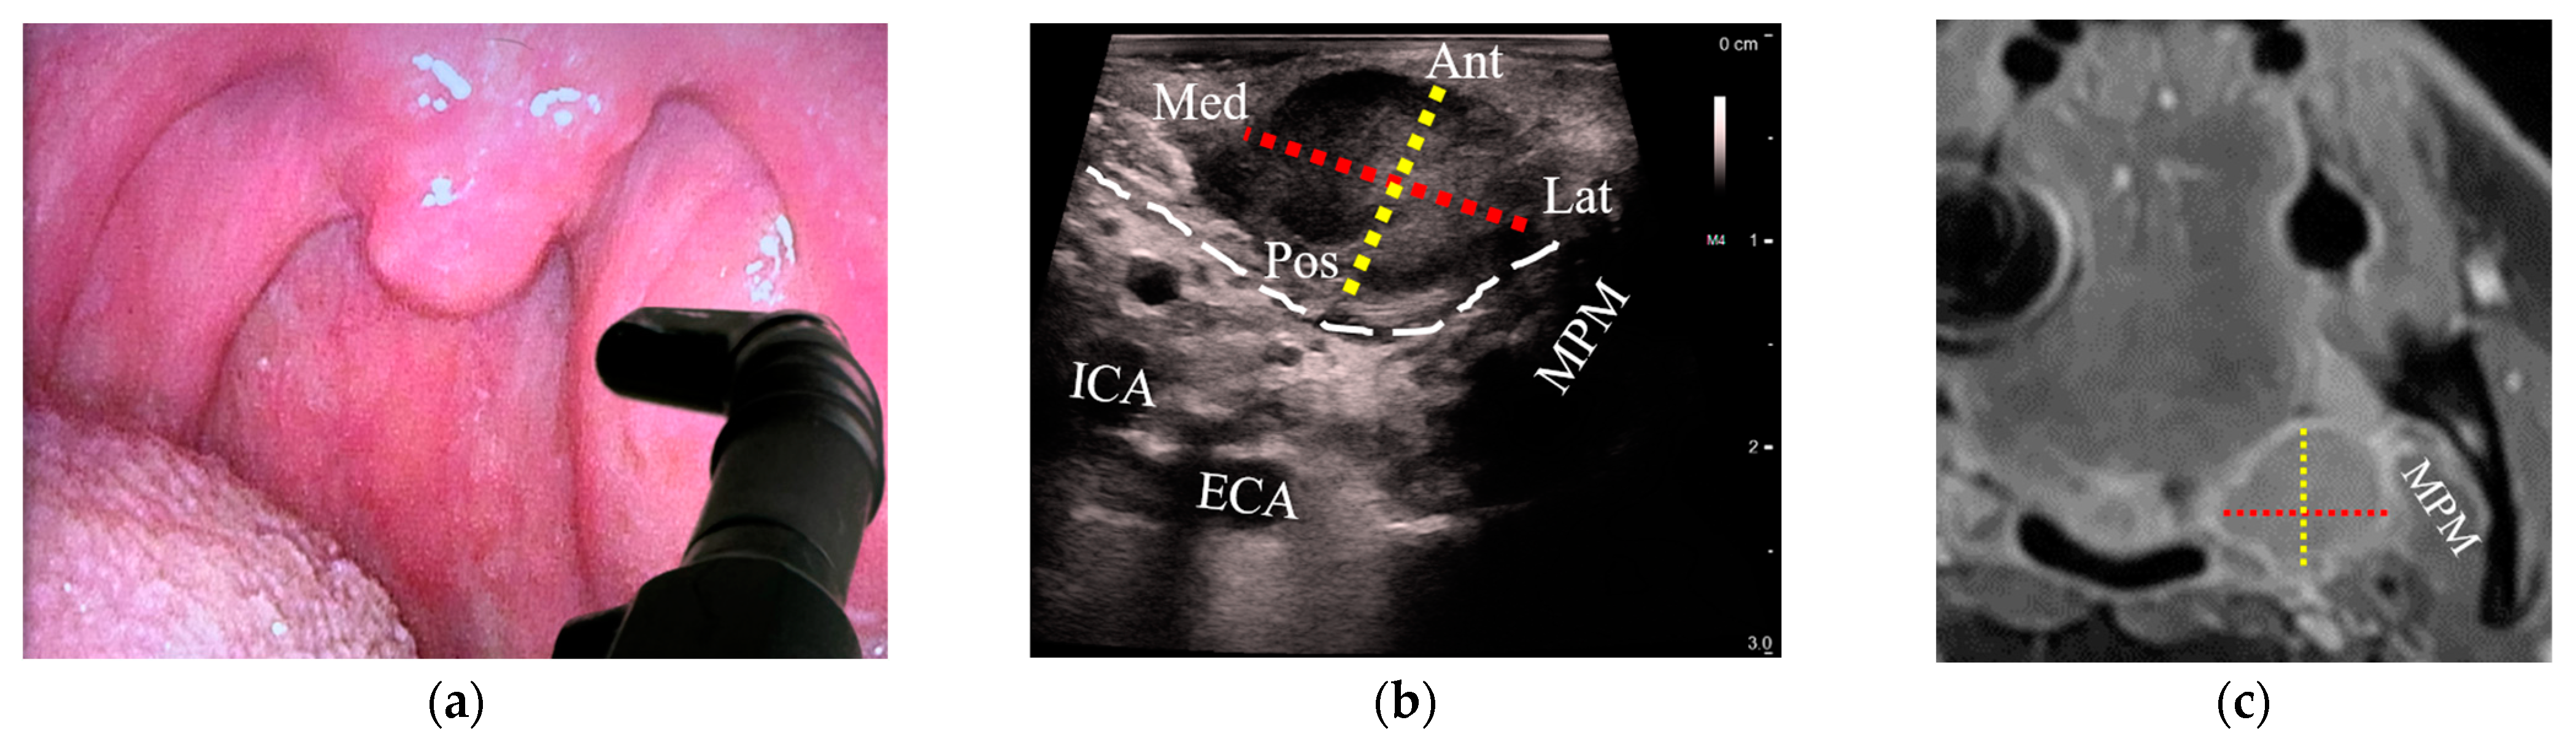

3.3. Detection of OPCs Compared between US and MRI

3.4. Comparison of T-Staging between US and MRI

3.4.1. Correlation of the Greatest Tumor Size

3.4.2. Agreement of Categorical T-Stage